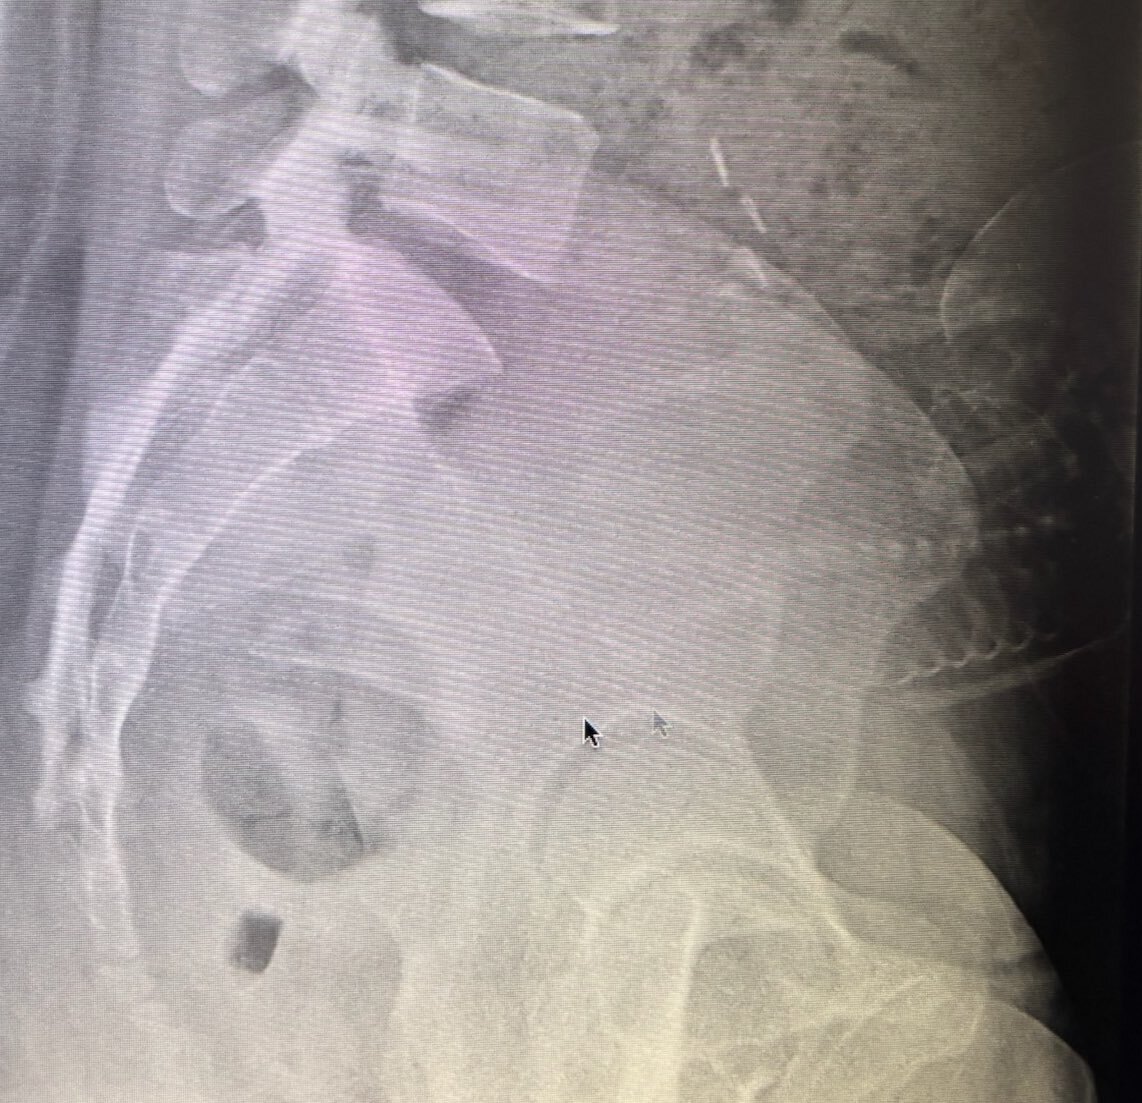

初めまして、通りすがり失礼します! お子さんのおてて、レントゲンでも分かるむちむちでとっても可愛くて癒されました🥰 少し違いますが、我が子も私の腰痛で安定期にレントゲンデビューし、親子初めてのツーショットとなったのを思い出しました💀 お子さんすくすく育ちますように👶🫶 pic.x.com/0ny0N5kZRt